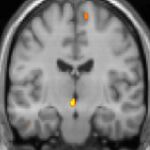

Positron emission tomography (PET) shows brain areas being activated during pain.

Positron emission tomography (PET) scans indicate the brain areas which are activated during attack only, compared to pain free periods. These pictures show brain areas that are active during pain in yellow/orange color (called "pain matrix"). The area in the center (in all three views) is activated only during cluster headaches. The bottom row voxel-based morphometry shows structural brain differences between individuals with and without CH; only a portion of the hypothalamus is different.[36]